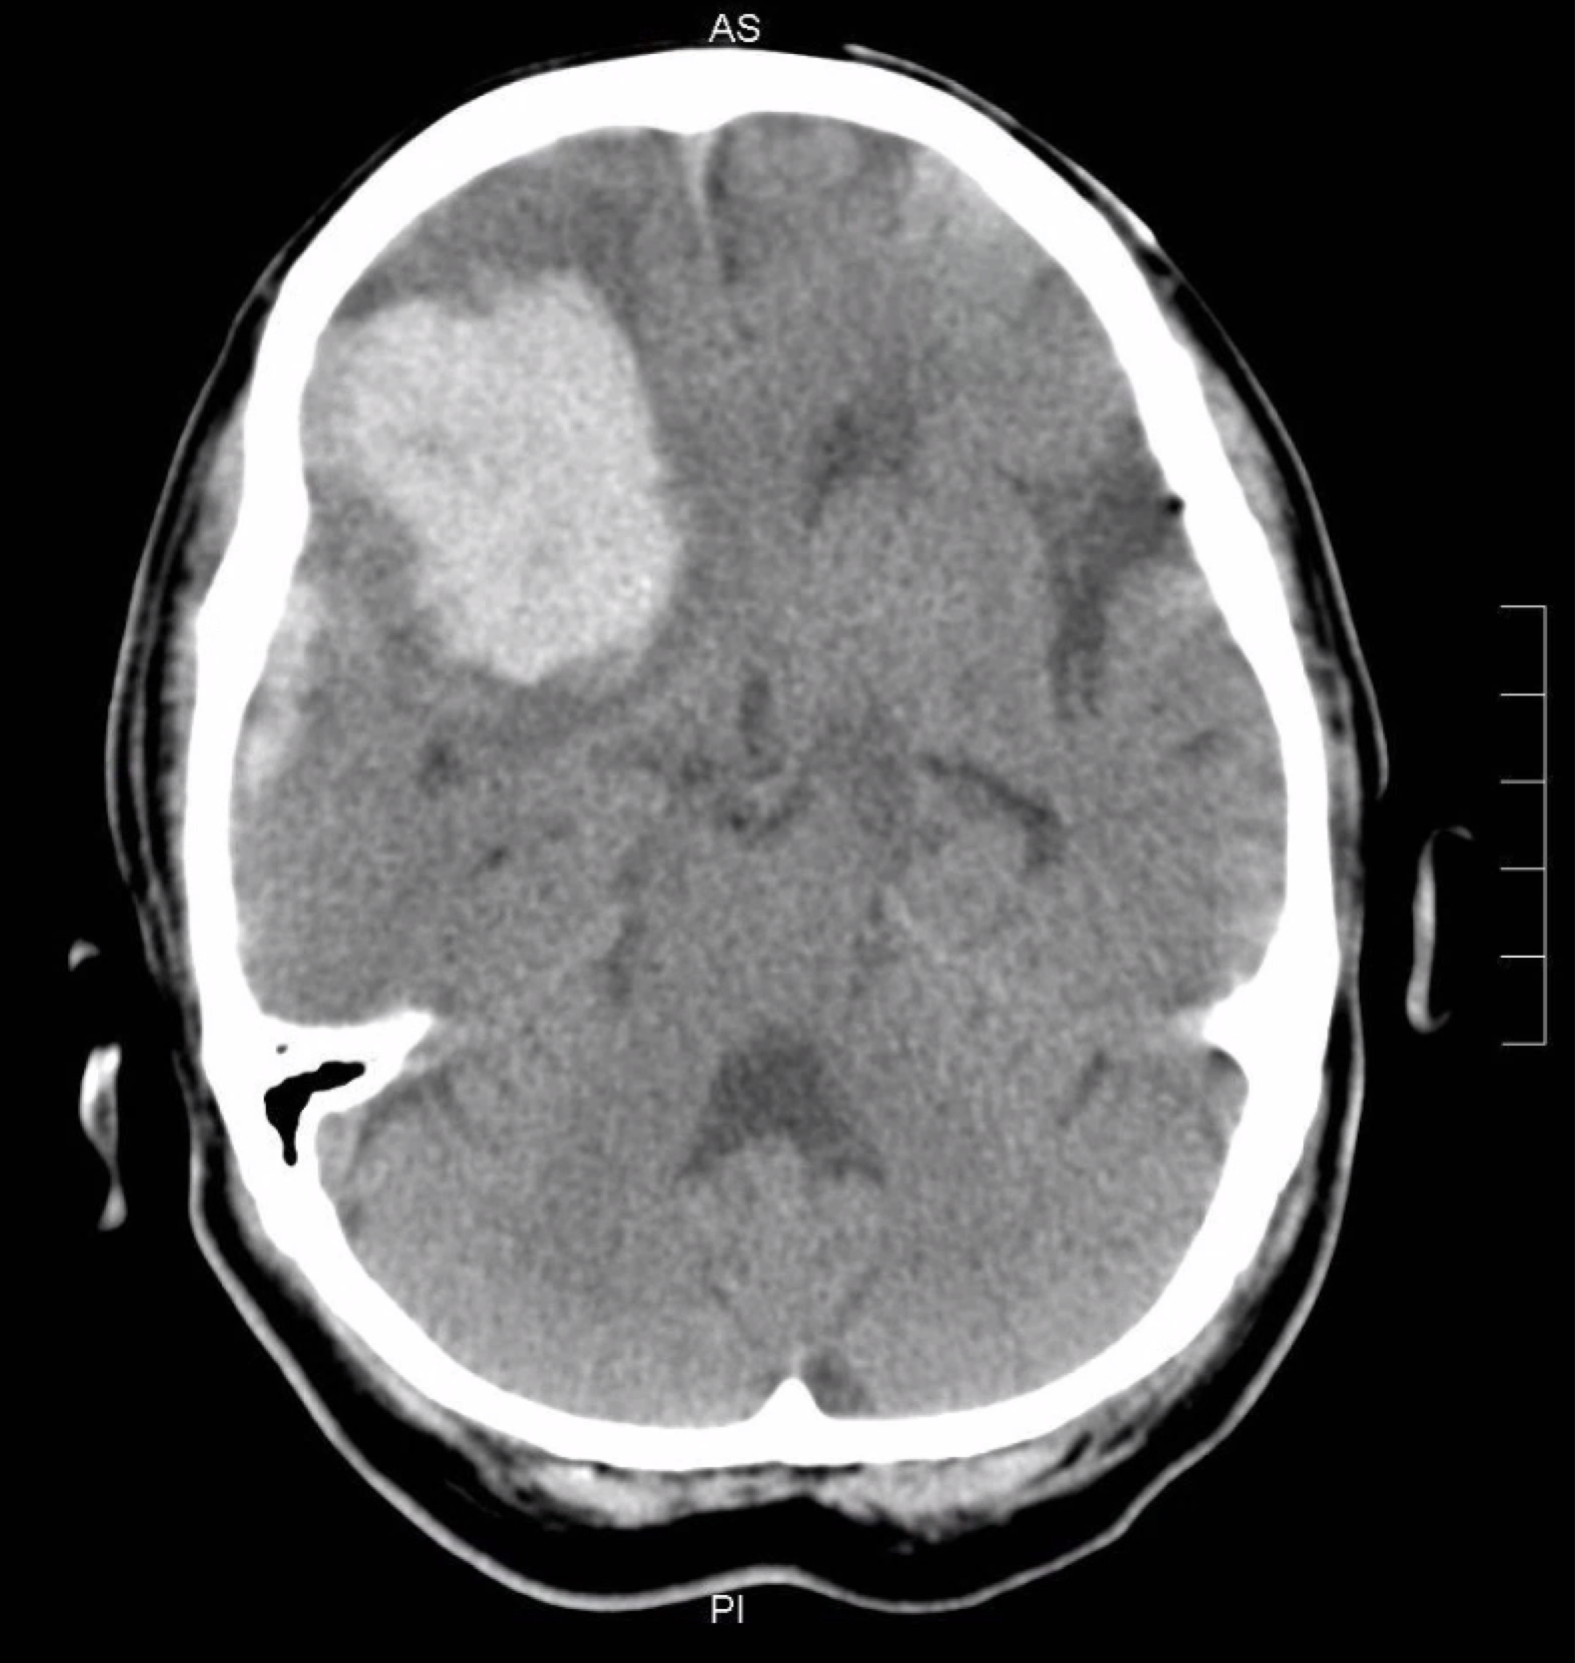

Left hemiplegia d/t right frontal ICH. SDH. 2020.10.30.

| BG ICH (0) | 2021.07.12 |